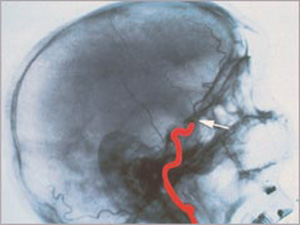

Egy agy röntgenképe

Egy halott agy röntgenképe

(Forrás: Deutsche Stiftung Organtransplantation, Neu-Isenburg

"Der Hirntod als der Tod des Menschen", Schlake/Roosen, Második kiadás, 2001)